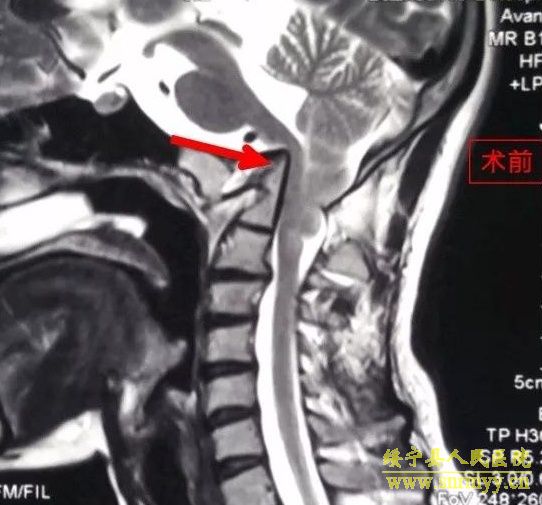

9月2日,我院神经外科在解放军昆明总医院封亚平教授的指导下,成功实施县内首台上颈椎、颅颈交接区手术,这标志着我院神经外科诊疗技术又迈上了一个新台阶。 40岁女性患者,因“头疼头晕伴左侧肢体麻木3年余,加重1月”入院,诊断为环枕畸形合并小脑扁桃体下疝。MRI及CT显示:枕颈融合,寰枢关节脱位,颅底陷入,颅颈角明显变小,小脑扁桃体下疝、延颈交界脊髓明显受压(如图下图所示),此病的症结是那块骨头(红色箭头处)压迫了神经! 想要解决问题,自然就得把那块骨头“掰”下来。骨头虽小,真要把它“掰”下来却绝非易事,需要把颈1-2的小关节撑开,但是,患者的小关节后面还有很粗大的动脉血管(蓝色箭头)挡着,手术难度相当大! 经解放军昆明总医院封亚平教授会诊,我院神经外科为该患者实施了后入路枕骨大孔区减压、寰枢椎脱位复位、枕颈固定、植骨融合术,手术用时短短1.5小时,出血量仅50ml。病人术后神经压迫症状明显改善,第一天开始进食,第二天即可下床活动。 (斜坡颈椎角增大到正常) (术后复查CT及MRI显示寰枢关节脱位复位理想,颅颈角增大基本正常,脊髓受压解除。) (术中无血管、神经损伤) 寰枕畸形是枕骨大孔区、寰枢椎骨质发育异常伴神经系统、椎动脉及附近软组织发育异常的一种先天性畸形疾病。寰枕畸形主要包:扁平颅底、颅底凹陷、寰枕融合、颈椎分节不全、寰枢椎脱位、小脑扁桃体下疝畸形。寰枕畸形可继发于畸形性骨炎、软骨病、佝偻病等。寰枕畸形患者早期临床表现为颈短、头颈痛、活动受限等。对于颈部粗而短的人群而言,寰枕畸形的发病可能相较一般人更高。原因在于,颈部粗短的人在转头活动的过程中,关节的活动度比较大,磨损的程度也更高,因而更容易发病。寰枕畸形合并小脑扁桃体下疝及脊髓空洞症为先天性发育不良所致,成年起病,无任何药物可治疗,手术是唯一有效的治疗办法。起初,患者会逐渐出现颈肩部疼痛,手臂麻木、无力,行走不稳等症。若不及时治疗,晚期预后会很差。(图为 邓泽亮 编辑 雅玲) 神经外科电话0739-2570859 科主任邓泽亮13975968148 副主任黄敏15211991811 |